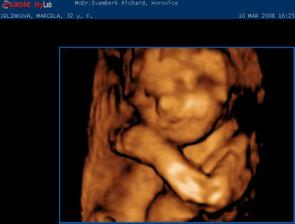

Jako v pohádce. 1.9.2007 jsme měli svatbu. 18.9.2007 jsme odjeli do Egypta na svatební cestu. Ze které jsme přijeli ve třech. Opravdu se nám to povedlo. 7.10.2007 jsem nedostala MS 10.10.2007 HURÁ !!!! Těhoteský test pozitivní. 12.11.2007 první KO, jsem 9+1 tt. Pan doktor mi dělal UTZ, dal mi první fotku mimíška. Těhotenství potvrzeno na 100 %,dostala jsem Těhotenskou průkazku. 29.11.2007 11+6 tt Byla jsem na odběru krve. Mám nízký tlak. 10.12.2007 13+3 tt KO viděla jsme opět mimíško na UTZ, má se čile k světu. Krev je vpořádku. 13.12.2007 potvrzení od obvodní lékařky a měření EKG. 3.1.2008 16+4 tt KO odběr krve na Triple test. UTZ mimíšku pěkně bije srdíško. Mám stále nízký tlak. Berou mě křeče do lýtek a pálí žáha. Pan doktor mi napsal MagneB6. 19.1.2008 18+6 tt už se pomalu do ničeho nevejdu. První nákup těhu kalhot a těhu blůza. 22.1.2008 19+2 tt dnes ráno jsme cítila jak mě mimíško několikrát koplo. A dopoledne v práci jsem cítila takové šimrání v bříšku. 28.1.2008 dneska jsem koupila mimíškovi první bodíčka. 31.1.2008 20+4 tt KO Trile test nagativní. Pan doktor mi dělal UTZ a pravděpodobně to bude KLUK. Poznala jsme to i já. Mimíško už váží 400g. Manžel měl radost. 4.2.2008 21+1 tt první těhotenské plavání. Bylo to moc pěkné a myslím, že i mimíšku v bříšku se to líbilo. 9.2.2008 – 16.2.2008 mám dovču. Jeli jsme na hory, ale já jsme raději nelyžovala, abych neublížila mimíšku. Vynahradím si to až příští rok. Hodně jsem odpočívala a chodila na procházky. 18.2.2008 kontrola u zubaře. Vše v pořádku. 19.2.2008 v práci mi bneska hodně tvrdlo a bolelo břicho. Tak uvidím jak mi bude zítra. 20.2.2008 23+3 tt opět mě tvrdlo a bolelo břicho až do zad. A docela intenzivně. Popráci jsem šla rovnou k doktoru. Vyšetřil mě a říkal, že to není moc dobré. Raději mi napsal neschopenku. 21.2.2008 bolí mě v kříži, především při chůzi. Jen doufám, že to nebude až do konce těhulkování. 27.2.2008 24+3 tt dneska jsem šla k obvodní doktorce s tou bolavou kyčlí. Stále mě dost bolí. Poslala mě na těhotenské cvičení, kde mi ukážou nějaké uvolňovací cviky a mám odpočívat. Snad to přejde. 5.3.2008 25+3 tt těhotenaké cvičení v nemocnici. Sestřička mi ukázala nějaké cviky na uvolnění kyčle a masáž. 10.3.2008 26+1 tt dneska jsme byli s manželem na 4 D UTZ. Bylo to moc hezké, mimíško se nám hezky ukázalo. Dokonce jsme viděli, že je to opravdu kluk. Pan doktor nám udělal nějaké fotky a nahrál mimíško na DVD. Je to opravdu moc krásný a jedinečný zážitek. 11.3.2008 26+2 tt dnes jsem byla v nemocnici na testu na cukrovku. 13.3.2008 začala jsme chodit do Solné jeskyně. Moc pěkně se tam relaxuje. Rozhodně to všem doporučuji. 19.3.2008 Dnes velký nákub oblečků na mimíško. 20.3.2008 27+4 tt KO test na cukr mám v normě. Tlak stále nízký a žáha mě pořád pálí. Bolest kyčle už ustoupila. Parvděpodobně mimíško změnilo polohu a netlačí už na nic. 29.3.2008 Byli jsme se podívat na kočárek. Nakonec se nám nejvíce líbí kočárek JANE SLALOM PRO, barva hnědooranžová. 10.4.2008 začala jsme chodit na těhu cvičení na Gymbalonech. 16.4.2008 první hodina předporodní přípravy. 17.4.2008 31+4 tt KO UTZ mimíško podle měření už váží 2100g, doufám, že to nebude žádný obřík. Jinak se má k světu a vše je v pořádku. Byla mi odebrána krev. 25.4.2008 32+5 tt pěkně mě bolí v krku. Návštěva obvodní lékařky. Udělala mi výtěr a uvidí podle výsledků. 28.4.2008 výtěr je vpořádku, ještě mě pro jistotu poslala na krční. Prý v těhotenství bývají zduřelé krční mandle. Tak by to mělo přejít samo. Mám brát pouze těhu vitamíny. Dneska jsme si přivezli kočárek. Nechali jsme ho u rodičů, pro jistotu, pověra je pověra, ale kdo ví. 4.5.2008 34 tt nástup na mateřskou dovolenou. Začínám s masáží hráze. 5.5.2008 34+1 tt KO UTZ mimíško už tam nemá moc místa, váží už 2500g, Mám nízké hodnoty železa v krvi. Tak jsem dostala vitamín železo. Magnesium už nemám brát. Dneska jsme byli s manželem v nemocnici, kde budu rodit, na předporodní besedě. Řekli nám, co nás čeká při porodu, a ukázali porodní pokoj. 8.5.2008 doma generální úklid a příprava na mimíško. Oblečky na mimíško mi pere a žehlí mamka, je moc hodná a hodně mi s tím pomáhá. Jsem moc ráda a tato práce mi odpadla a já si domů odvezu už vše hotové. 9.5.2008 34+5 tt celou noc jsem nespala, mám rýmu a strašný kašel. Docela se bojím i o mimíško. Tak jsem raději šla k obvodní doktorce. Ta mě poslechla, mám zánět průdušek. Dala mi antibiotika ZINNAT 250mg. Moc nejsem nadšená. Ujišťovala mě, že se můžou v těhotenství, a i v lékárně mi to říkali. Doma jsem si to našla i na Internetu. Tak snad bude vše vpořádku. 12.5.2008 35+1 tt Dneska jsem byla na natočení na EKG, to prý potřebuji k porodu. 13.5.2008 Opět mě začal bolet kyčel, jak mě již jednou bolel. Asi se mimíško nějak jinak uvelebuje a tlačí mi na nějaký nerv. 15.5.2008 35+4 tt KO doktor říkal, že mě ta kyčel pravděpodobně přestane bolet až po po porodu. Tak nejsem moc šťastná, protože je to dost omezující, především při chůzi. Mimíško je vpořádku. Dneska mi poprvé natáčel monitor, tak jsem slyšela tlukot mimíškova srdíčka. 26.5.2008 37+1 tt Dneska mám narozeniny!!! KO pan doktor mi dělal vyšetření a kultivaci z pochvy. Od příštího týdne už budu chodit na KO do nemocnice, kde také budu rodit. Tak už jsme se rozloučili a mám k němu přijít na KO až po šestinedělí. Snažím se, co nejvíce odpočívat. 2.6.2008 38+1 tt KO už v nemocnici. Výsledky kultivace nejsou moc dobré, tak jsem dostala globule na zavádění. S paní doktorkou jsme se domlouvali na průběhu porodu, protože jsem v minulosti měla zlomenou sedací kost. Domluvili jsme se, že porod necháme přírodní cestou a pokuď bude něco špatně, tak přistoupí k císařskému řezu. Doufám, že bude vše bez komplikací. Opět mi natáčeli monitor. 9.6.2008 39+1 tt KO natáčení monitoru. Je moc hezké slyšet jak mimíšku bije srdíčko. Dneska mi dělala vyšetření, vše je vpořáku. Zítra jdu na UTZ. 10.6.2008 39+2 tt dneska jsem byla na UTZ, kde měřili mimíško. Podle měření váží asi 3509g. Nakonec jsme se s paní doktorkou domluvili, že pokud neporodím do 22.6., tak si v pondělí 23.6. v 8 hodin půjdu lehnout do nemocnice, abych moc dlouho nepřenášela a mimíško nebylo moc velké, vzhledem k té zlomené sedací kosti. No nějak mi to těhulkování moc rychle uteklo a už se ten obávaný porod opravdu blíží, což si nějak moc nechci připouštět. Ale můžu říci, že jsem si to moc užila a ještě užívám. Je to asi opravdu ta nejkrásnější doba v mém životě. Vědět, že v sobě máte mimíško, a těšit se na něj. 16.6.2008 40+1 tt tak dneska už jsme byla na natočení monitoru a na poslední KO. Doktorka mi dělala vyšetření a říkala jak miminko je hezky sestouplé. Prý je dobře připraveno k porodu a vše vypadá, že bych mohla porodit dříve než v pondělí. Aby mi nemuseli porod vyvolávat. Já bych raději chtěla porodit normálně bez vyvolání. Doufám, že se to povede. Jinak v pondělí 23.6.2008 nastupuji do nemocnice. No tak musíme doma zkusit osvědčené babské rady, snad se nám to povede. Mimíško se nějak v bříšku zabydlelo a vůbec se mu nechce ven. Držte nám palečky. Děkujeme. 17.6.2008 40+2 tt od 23.00 hod tvrdnutí bříška, že by to již bylo ono???? Ve 23.43 hod začínají kontrakce po 10 minutách. 18.6.2008 40+3 tt ve 2.30 hod odjezd do porodnice. Kontrakce po 4,5 minutách. V 8.29 hodin DAVÍDEK na světě. Váží 3880g a měří 52 cm. Tatínek byl u porodu a byl moc velkou oporou mamince. Moc si toho vážím. Je to velká odměna a stálo to za to. Těď už jsem ne dva, ale tři. Jedna velká rodina. Jsme moc šťastni.